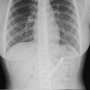

Global Times melaporkan hasil CT scan menunjukkan adanya penumpukkan tulang ikan di areal rektum lelaki berusia 60an tersebut.